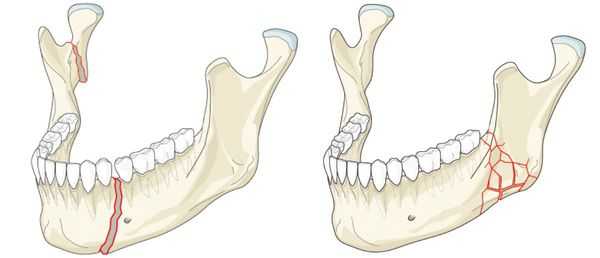

Переломы могут быть закрытыми и открытыми, а также неполными и полными.

Неполный и полный переломы костей

При полном переломе кость разделяется на 2 части. Типы полного перелома:

- одиночный перелом, при котором кость ломается в одном месте на 2 части

- оскольчатый перелом, при котором кость ломается на 3 или более частей

- сегментарный перелом — кость сломана в двух местах таким образом, что по крайней мере один сегмент выходит из нормального положения.